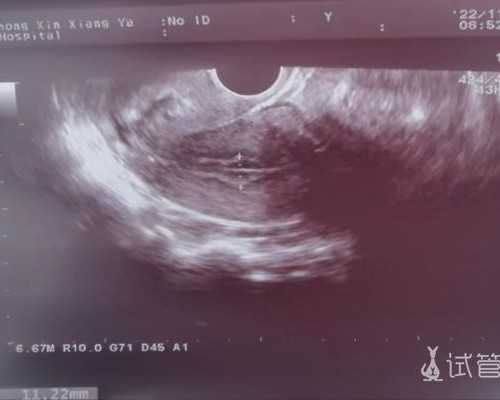

中信湘雅:截至2026年,中信湘雅试管婴儿总治疗量已达42万多个周期,助孕婴儿总数已超过18万个,试管婴儿平均妊娠率为62.3%,可同时进行一、二、三代试管;